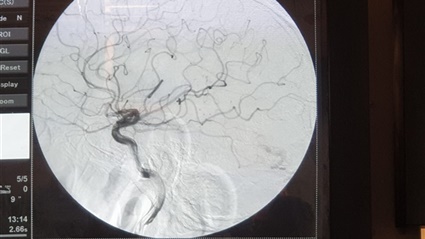

وأشار الدكتور حسان النعماني عميد كلية الطب البشري، إلى أن الدكتور أحمد بسيوني قام بإجراء قسطرة على شرايين المخ لحالتين بوحدة القسطرة بالمستشفى الجامعى احداهما لنزيف بالمخ اصاب شاب يبلغ من العمر ٢٠ عام وتبين انه يعانى من تشوه شريانى وريدى بالمخ، والأخرى لمريض يبلغ ٨٠ عام يعانى من جلطات متكررة حيث تبين وجود ضيق شديد بالشريان السباتى الايسر.

ومن جانبه أوضح الدكتور غريب فاوي رئيس قسم المخ والاعصاب والطب النفسي بكلية الطب ان القسطرة المخية احدي الوسائل العلاجية التي تفيد في علاج العيوب الخلقية للمخ، وايضاً علاج الجلطات الدماغية وازالتها، فالقسطرة المخية التشخيصية توفر صور الأوعية الدموية للمخ أو الرأس، لتشخيص العيوب الخلقية الموجودة في الشرايين والاوردة المخية مثل التمدد الشرياني وتمدد الوصلات الشريانية الوريدية.